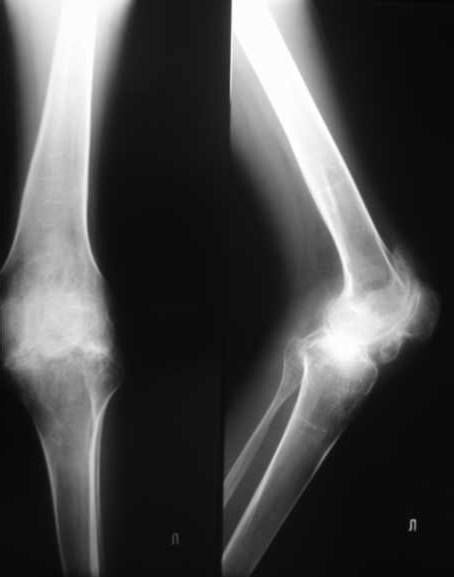

Уважаемые коллеги. пациент, страдает ревматоидным артритом с детства, ранее докладывался... костный анкилоз т/б суставов. 4 месяца назад THR левого т/б сустава, движения в т/б суставе приличные - с/р 90/5/0, движения в коленном суставе ухудшились - с/р 120/45/0. В настоящее время конечность неопорна из-за сгибательной кнтрактуры в к/с Вопросы о дальнейшей тактике лечения (пациенту 28 лет):1. рассматриваются варианты остеотомий (бедра, б/б кости), насколько это целесообразно, учитывая необходимость артротомии (остеофиты), каков может быть ожидаемый результат? варианты остеотомий (бедро или голень)?2. эндопротезирование к/с: мягкотканный дисбаланс- достаточно будет релиза капсулы и связок или мышцы тоже (учитывая разгибание в т/б после эндопротезирования и натяжение мышц на уровне колена после этого) Чего опасаться и к чему быть готовым?3. другие варианты? ссылки на литературу?собств наблюдения?С уважением Максим Агалаков